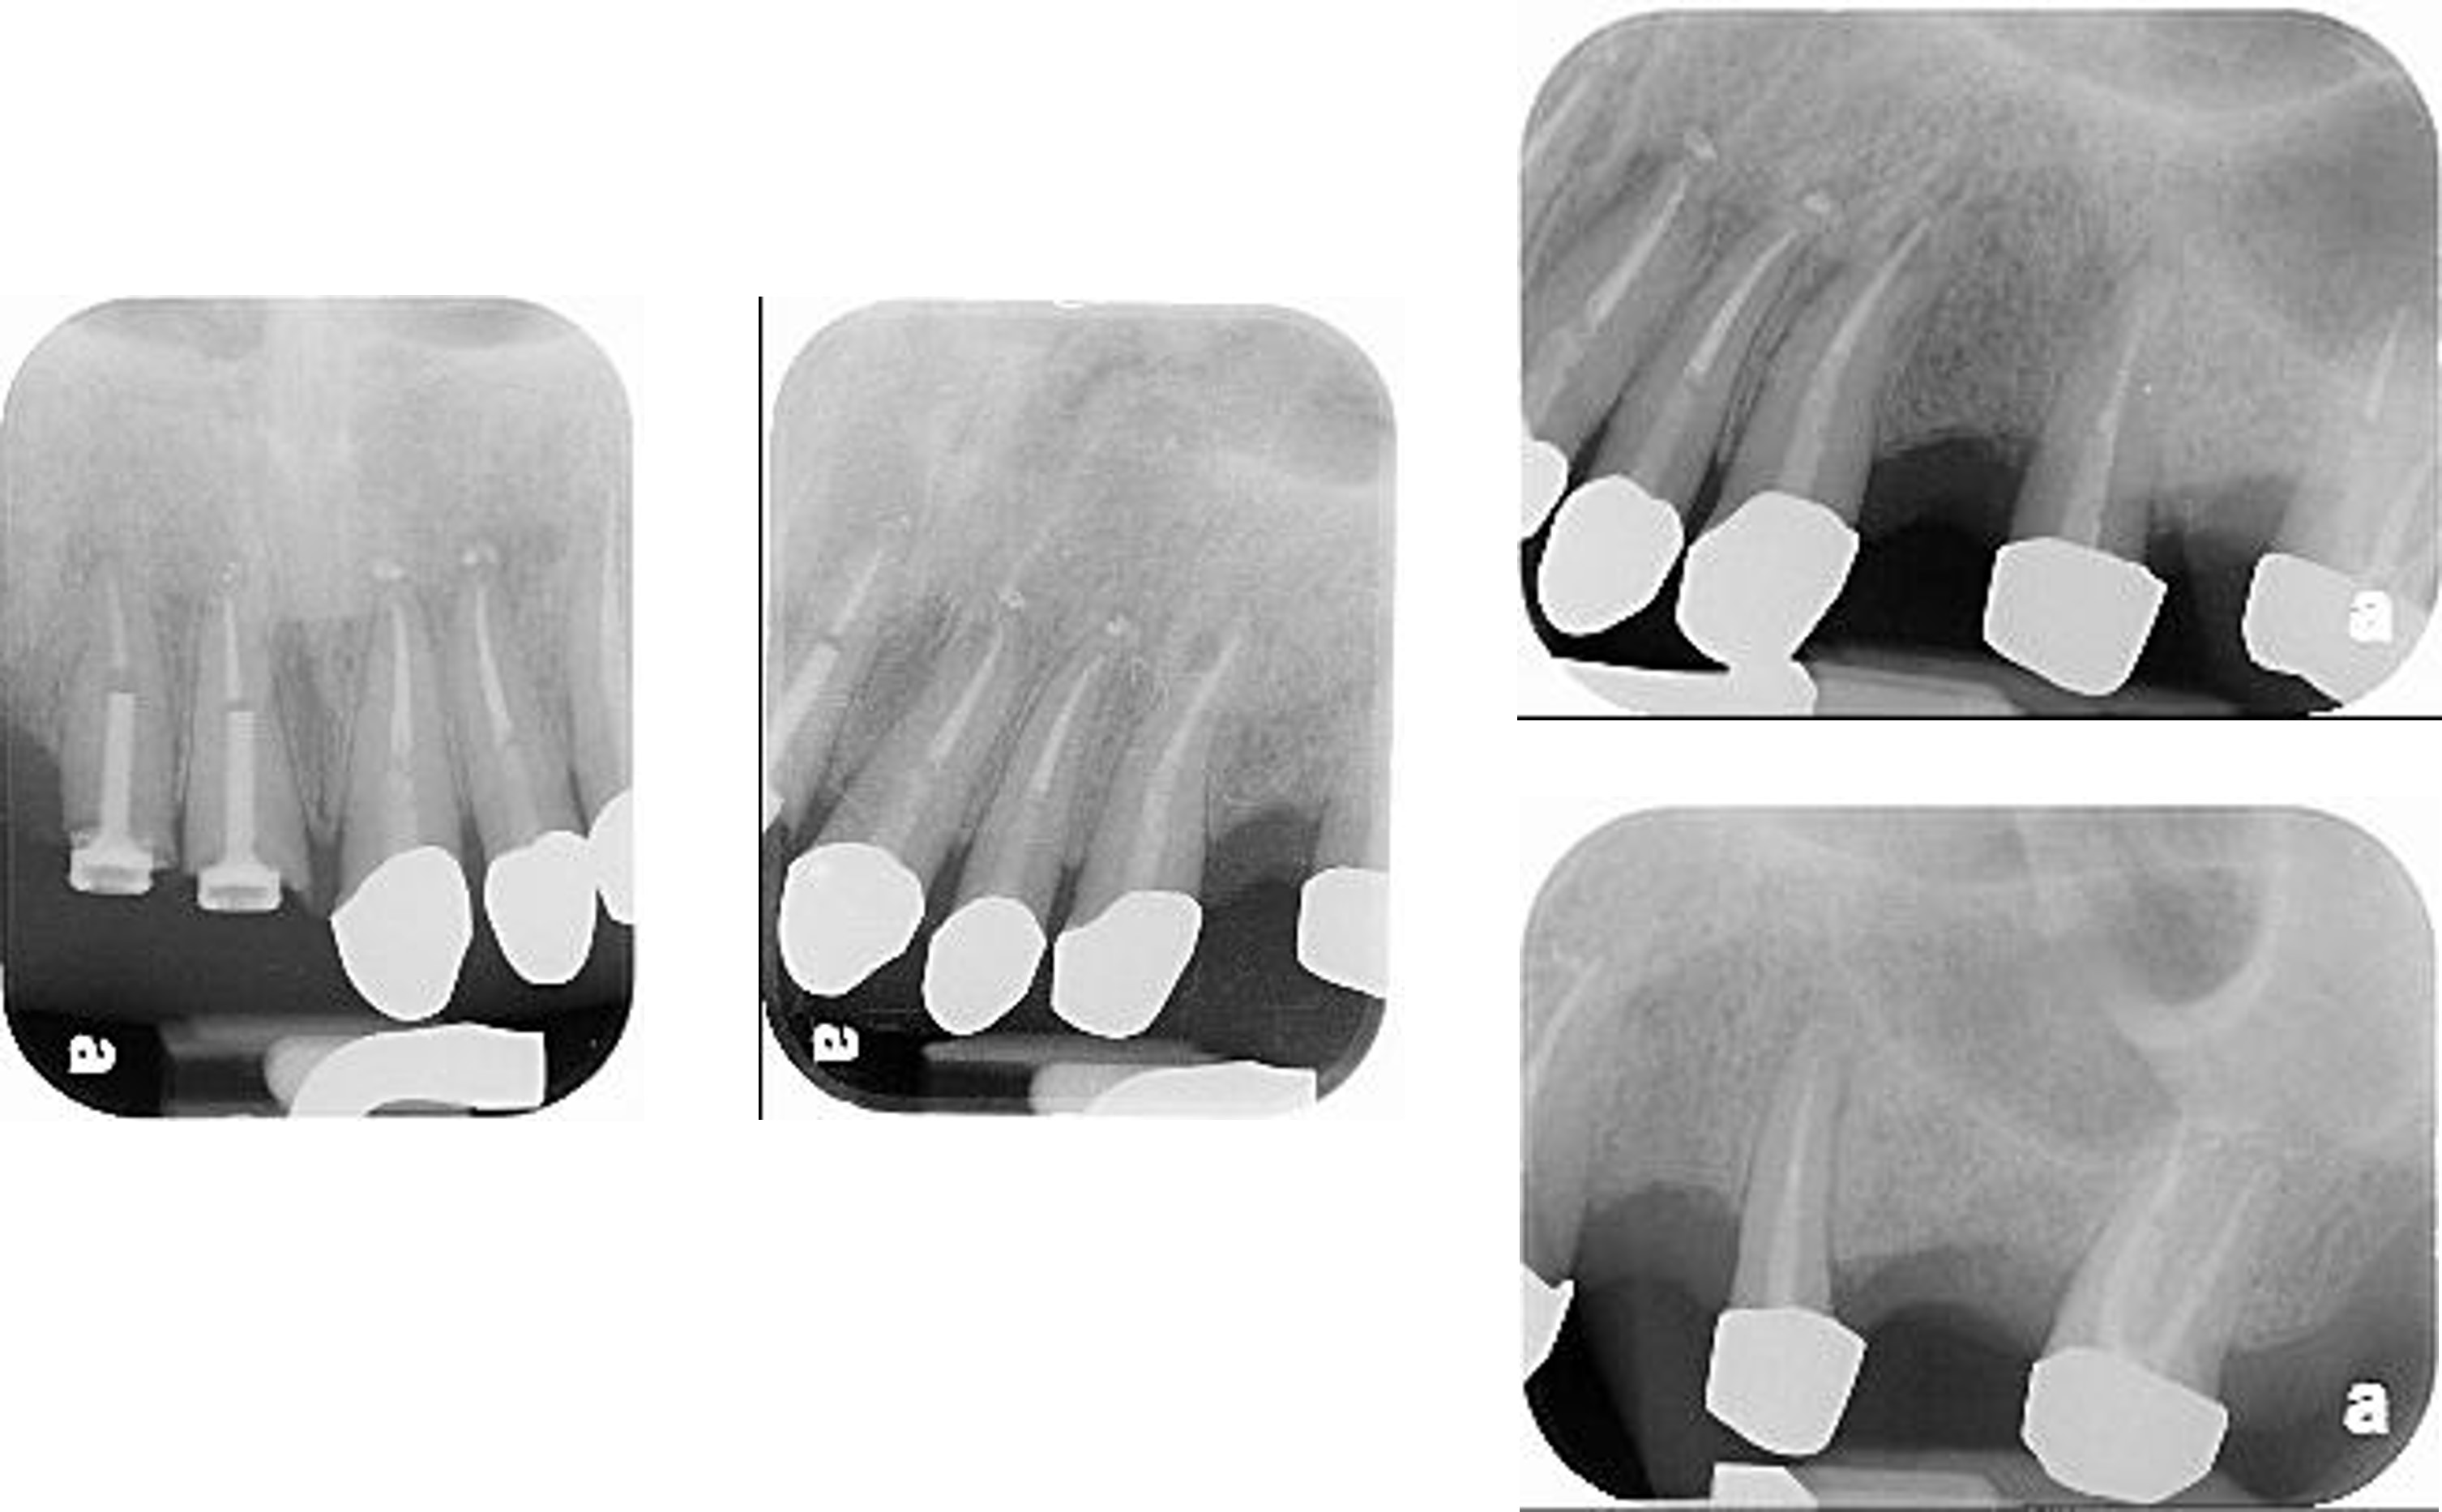

治療前上下顎因口外手術,造成咬合喪失

治療前,咬合喪失,磨耗

治療前,殘根與牙周支撐不良